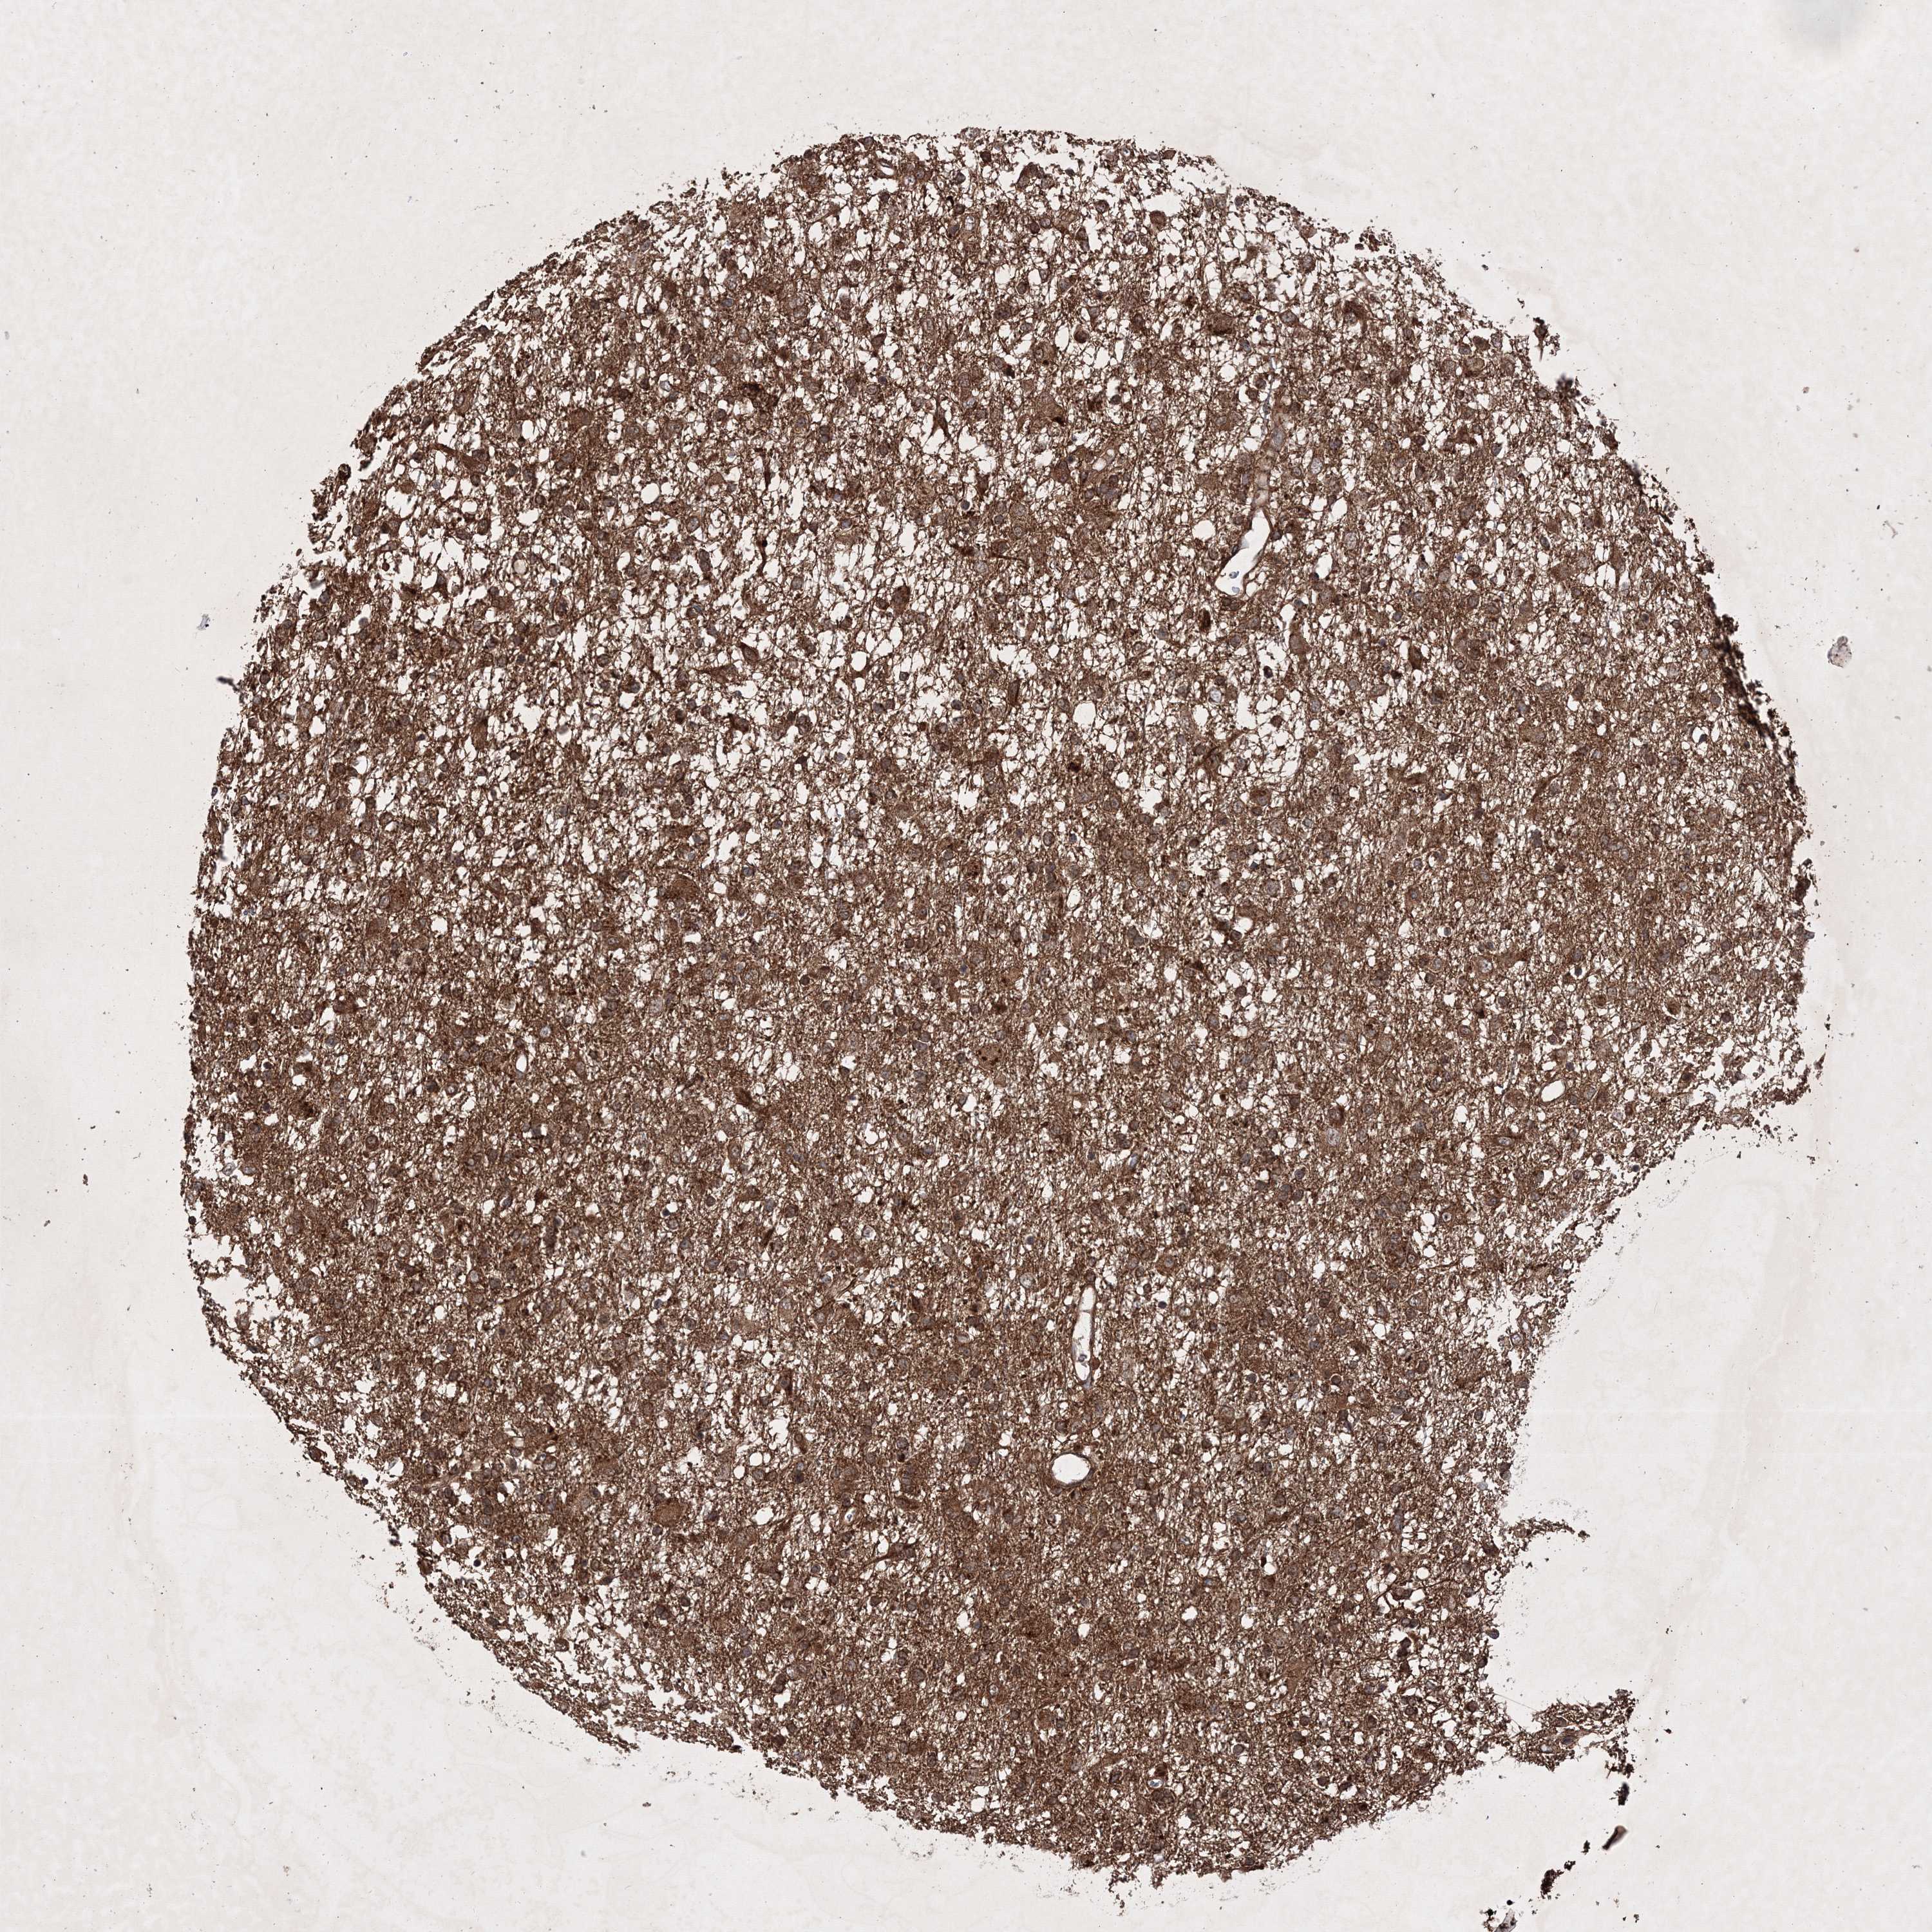

GLIOMA - Protein expressioni

A mouse-over function shows sample information and annotation data. Click on an image to view it in a full screen mode. Samples can be filtered based on level of antibody staining by selecting one or several of the following categories: high, medium, low and not detected. The assay and annotation is described here.

Note that samples used for immunohistochemistry by the Human Protein Atlas do not correspond to samples in the TCGA dataset.

Antibody stainingi

Antibody staining in the annotated cell types in the current human tissue is reported as not detected, low, medium, or high, based on conventional immunohistochemistry profiling in selected tissues. This score is based on the combination of the staining intensity and fraction of stained cells.

Each image is clickable and will lead to virtual microscopy that enables deeper exploration of all samples and also displays staining intensity scores, fraction scores and subcellular localization as well as patient and tissue information for each sample.

Antibody HPA036923

Antibody HPA036924

Staining

High

Medium

Low

Not detected

Intensity

Strong

Moderate

Weak

Negative

Quantity

>75%

75%-25%

<25%

None

Location

Nuclear

Cytoplasmic/membranous

Cytoplasmic/membranous,nuclear

Glioma, malignant, High grade

Glioma, malignant, Low grade

Glioblastoma, NOS